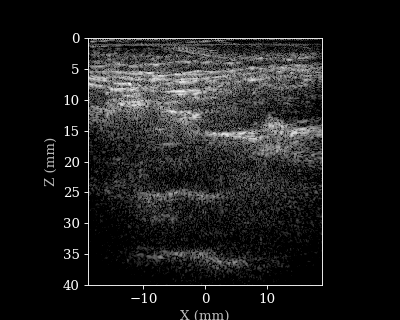

We will load a sequence of acquired RF data frames (carotid scan) and reconstruct a B-mode image from each frame. We will then animate the sequence of images. But first let’s load the data and parameters.

B-mode sequence